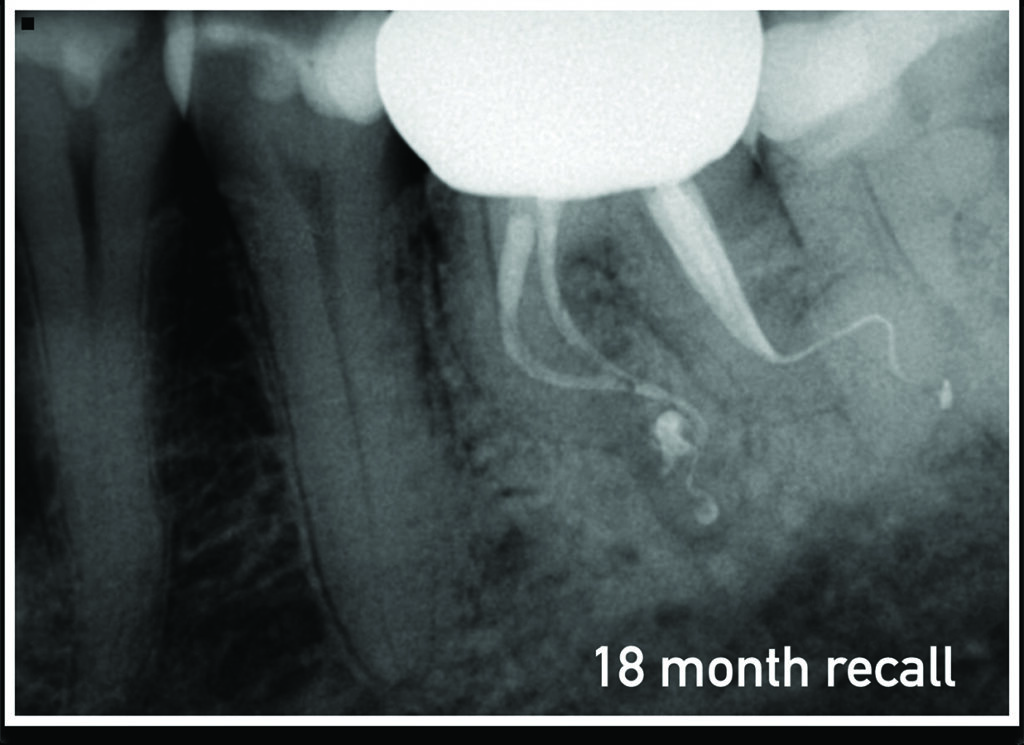

Successful Endodontic Management Using Er,CrYSGG Laser Disinfection of Laser Endodontic Disinfection Root canal treatment is the most effective and widely used method for controlling infection, promoting periapical healing, and. The efficacy of laser therapy applications in root canal disinfection with or without various irrigants protocols remains. Nd:yag laser (1064 nm) has been the most widely investigated laser for. Conventional laser use inside the root canal as an additional disinfection method;. Laboratory. Laser Endodontic Disinfection.